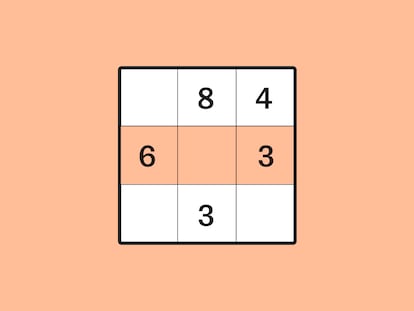

Curiosamente, son los tumores no sólidos, los que no se concentran en un órgano, los que están dando más alegrías en este abordaje. Un nuevo medicamento, el obinutuzumab, ha sido aprobado esta semana por el Ministerio de Sanidad español para tratar la leucemia linfática crónica (LLC), el más común de los tumores hematológicos, que afecta a 30 personas por cada millón de habitantes cada año. Actúa de dos maneras. Se trata de lo que se denomina un anticuerpo monoclonal. Esto quiere decir que está diseñado para unirse específicamente a las células tumorales, como hacen os anticuerpos que reconocen concretamente cada virus o bacteria que infecta un organismo. Una vez establecida la unión, actúa de dos maneras: señala la diana para el sistema inmunitario, y, también, él mismo tiene una cierta acción de destrucción de las células. El resultado es que la capacidad de "negativizar la enfermedad", de curarla, pasa del 3,3% con el tratamiento actual al 37,7%, dijo Francesc Bosch, el hospital Vall d'Hebron, al presentarlo. El riesgo de muerte se reduce un 61% frente a la medicación que se utiliza ahora.

Otro tratamiento que modula la respuesta inmune es el de la lenalidomida en pacientes con mieloma múltiple. Este medicamento es algo anterior, y ya se había probado en pacientes para los que había fracasado la terapia disponible. La lenalidomida, que es un regulador de la respuesta inmune, se administra combinada con dexametasona (una quimioterapia) y consigue, cuando se utiliza como primera opción, pasar del 13% de pacientes libres de progresión de la enfermedad a los cuatro años, a un 33%. Este uso se probó en España hace un mes.